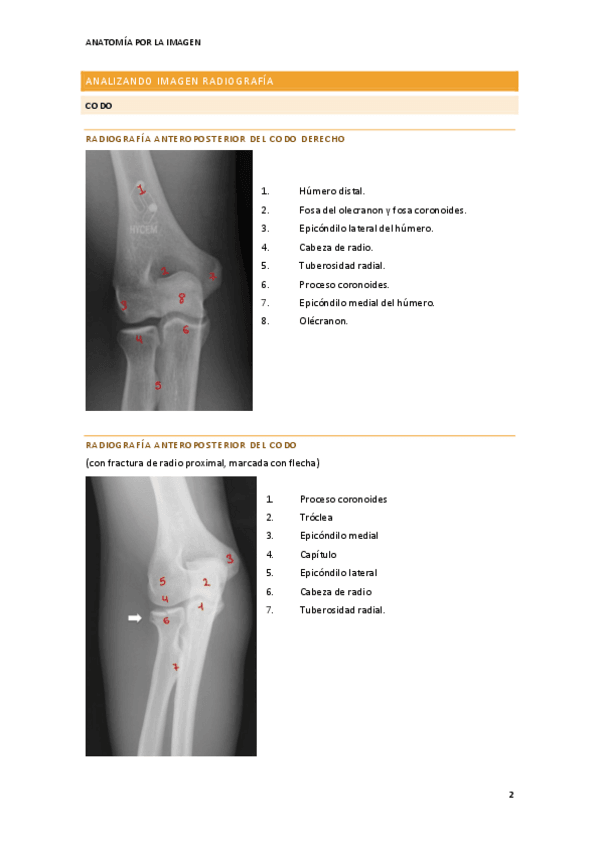

He publicado nuevos apuntes de Anatomía por la Imagen: tema-3-reconocimiento-estructuras-anatomicas-del-aparato-locomotor.pdf

18 páginas